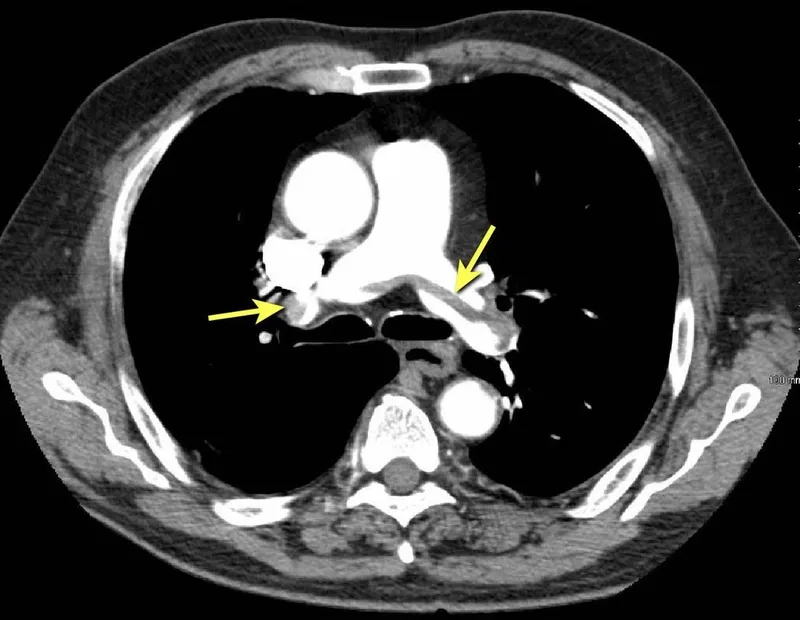

- First-line: CTPA - sensitivity 83%, specificity 96%

- V/Q scan if: contrast allergy, renal impairment (eGFR <30), pregnancy with normal CXR

CTPA vs V/Q Selection

| Factor | CTPA | V/Q Scan |

|---|---|---|

| First-line | ✓ | |

| Renal impairment (eGFR <30) | ✓ | |

| Contrast allergy | ✓ | |

| Pregnancy with normal CXR | ✓ | |

| Availability | Widely available | Limited centres |

✓ CTPA is first-line imaging; V/Q scan reserved for renal impairment, contrast allergy, or pregnancy with normal CXR